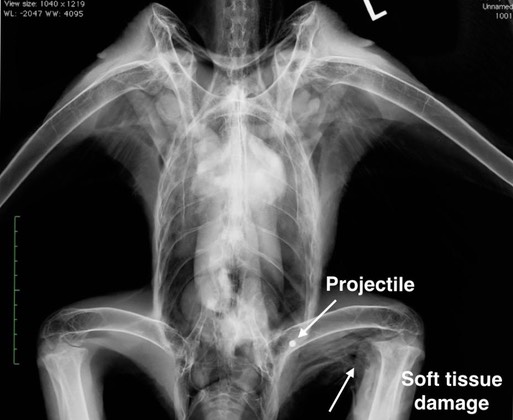

Bald Eagle 19-008

The first lead poisoned eagle of the year was admitted this past week. A call came from Pioneer Veterinary Clinic in Moses Lake, WA on Friday. Washington Fish and Wildlife had dropped off a Bald Eagle with an old infected laceration on his left leg. They took a radiograph and determined the eagle’s leg was not broken, but they did find evidence that he had been shot!

BMW’s intake protocol calls for a physical exam, radiographs and blood work. In addition to the laceration and evidence of a gunshot injury, the eagle’s blood lead level was 92.4 micrograms/deciliter, more than four times what is considered to be a toxic level of lead.